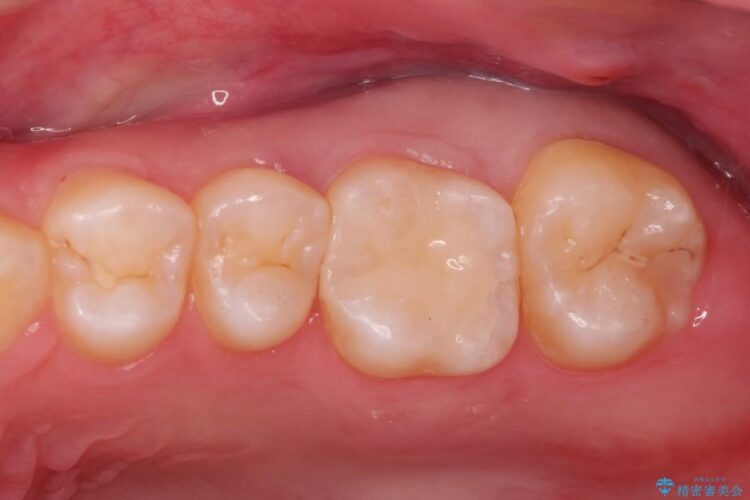

自然な見た目のセラミックインレーで精密に修復

自然な見た目のセラミックインレーで精密に修復 ビフォー 自然な見た目のセラミックインレーで精密に修復 アフター

右上5番に小さな穴があるとご相談にいらした患者様です。